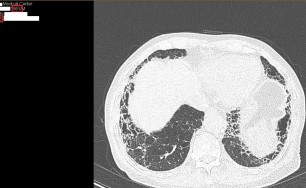

숨케어한의원에서는 전화예약을 받고 있습니다. 내원시 엑스레이, CT사진, 폐기능검사지를 가지고 오시면 자세한 상담이 가능합니다.